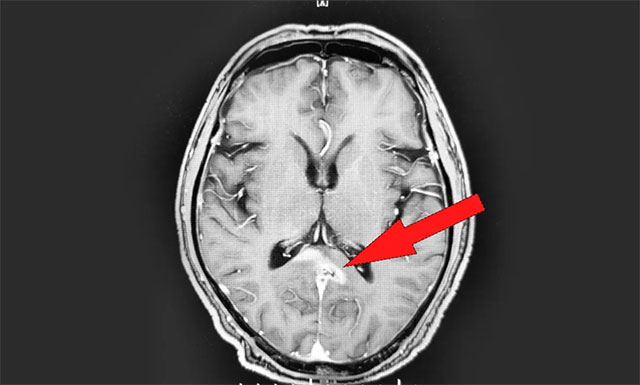

年過六旬的男性患者江某(化名),于2018年進(jìn)行體檢時(shí)被告知脾臟腫大,但由于當(dāng)時(shí)并無不適癥狀,患者沒有太在意。2019年11月中旬,患者突感身體不適,頭暈胸悶惡心,就診于當(dāng)?shù)蒯t(yī)院。行頭顱增強(qiáng)核磁檢查后,診斷其為胼胝體壓部及右側(cè)丘腦淋巴瘤,當(dāng)時(shí)暫未發(fā)現(xiàn)轉(zhuǎn)移跡象。

▲ 放療前 MRI 影像